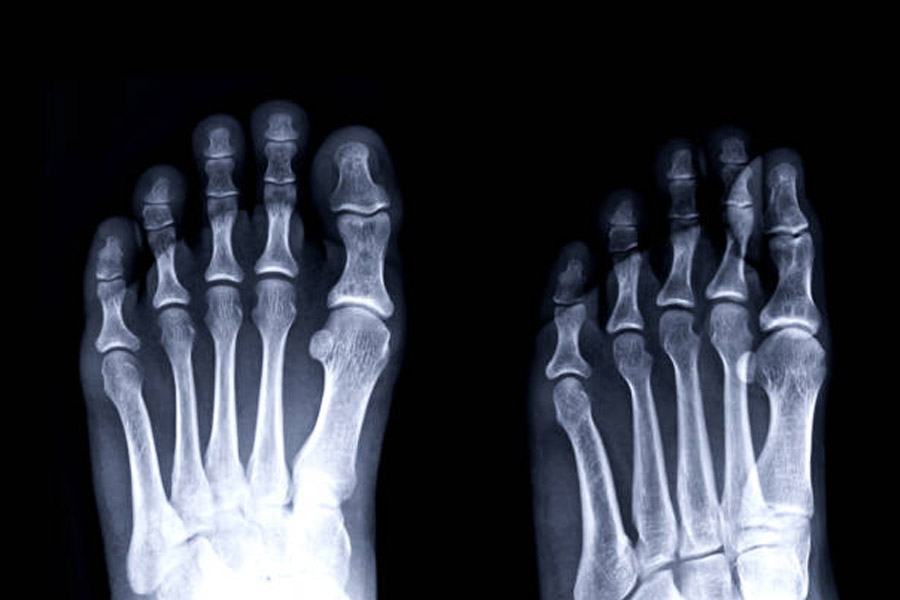

ডেভিডকে উদ্ধার করে সঙ্গে সঙ্গে হাসপাতালে নিয়ে যাওয়া হয়। চিকিৎসকেরা পরীক্ষা করে দেখেন, তাঁর বুড়ো আঙুলটির হাড়ে চিড় ধরে গিয়েছে। বুলডগের কামড়েই এমনটা হয়েছে বলে জানান চিকিৎসকেরা।

চিকিৎসকেরা পরীক্ষা-নিরীক্ষার পর জানান, বৃদ্ধের পায়ের ওই অংশে দু’টি ধমনী বন্ধ হয়ে গিয়েছিল। সেখান দিয়ে কোনও রকম রক্ত চলাচল করছিল না। সেই কারণেই তাঁর পা কিছু সময়ের জন্য অবশ হয়ে পড়েছিল।

অনুভূতি না থাকায় পায়ের এই সমস্যার কথা বুঝতেও পারেননি বৃদ্ধ। চিকিৎসকেরা জানান, কম জায়গা জুড়ে হওয়ায় চট করে এই অবশ ভাব নজরে আসত না। আর এই অবস্থায় বৃদ্ধের পা যদি বিনা চিকিৎসায় বেশি দিন পড়ে থাকতেন, তবে রক্ত সঞ্চালন বন্ধ হয়ে সম্পূর্ণ পা কেটে বাদ দেওয়ার মতো পরিস্থিতি হতে পারত। হতে পারত মৃত্যুও।